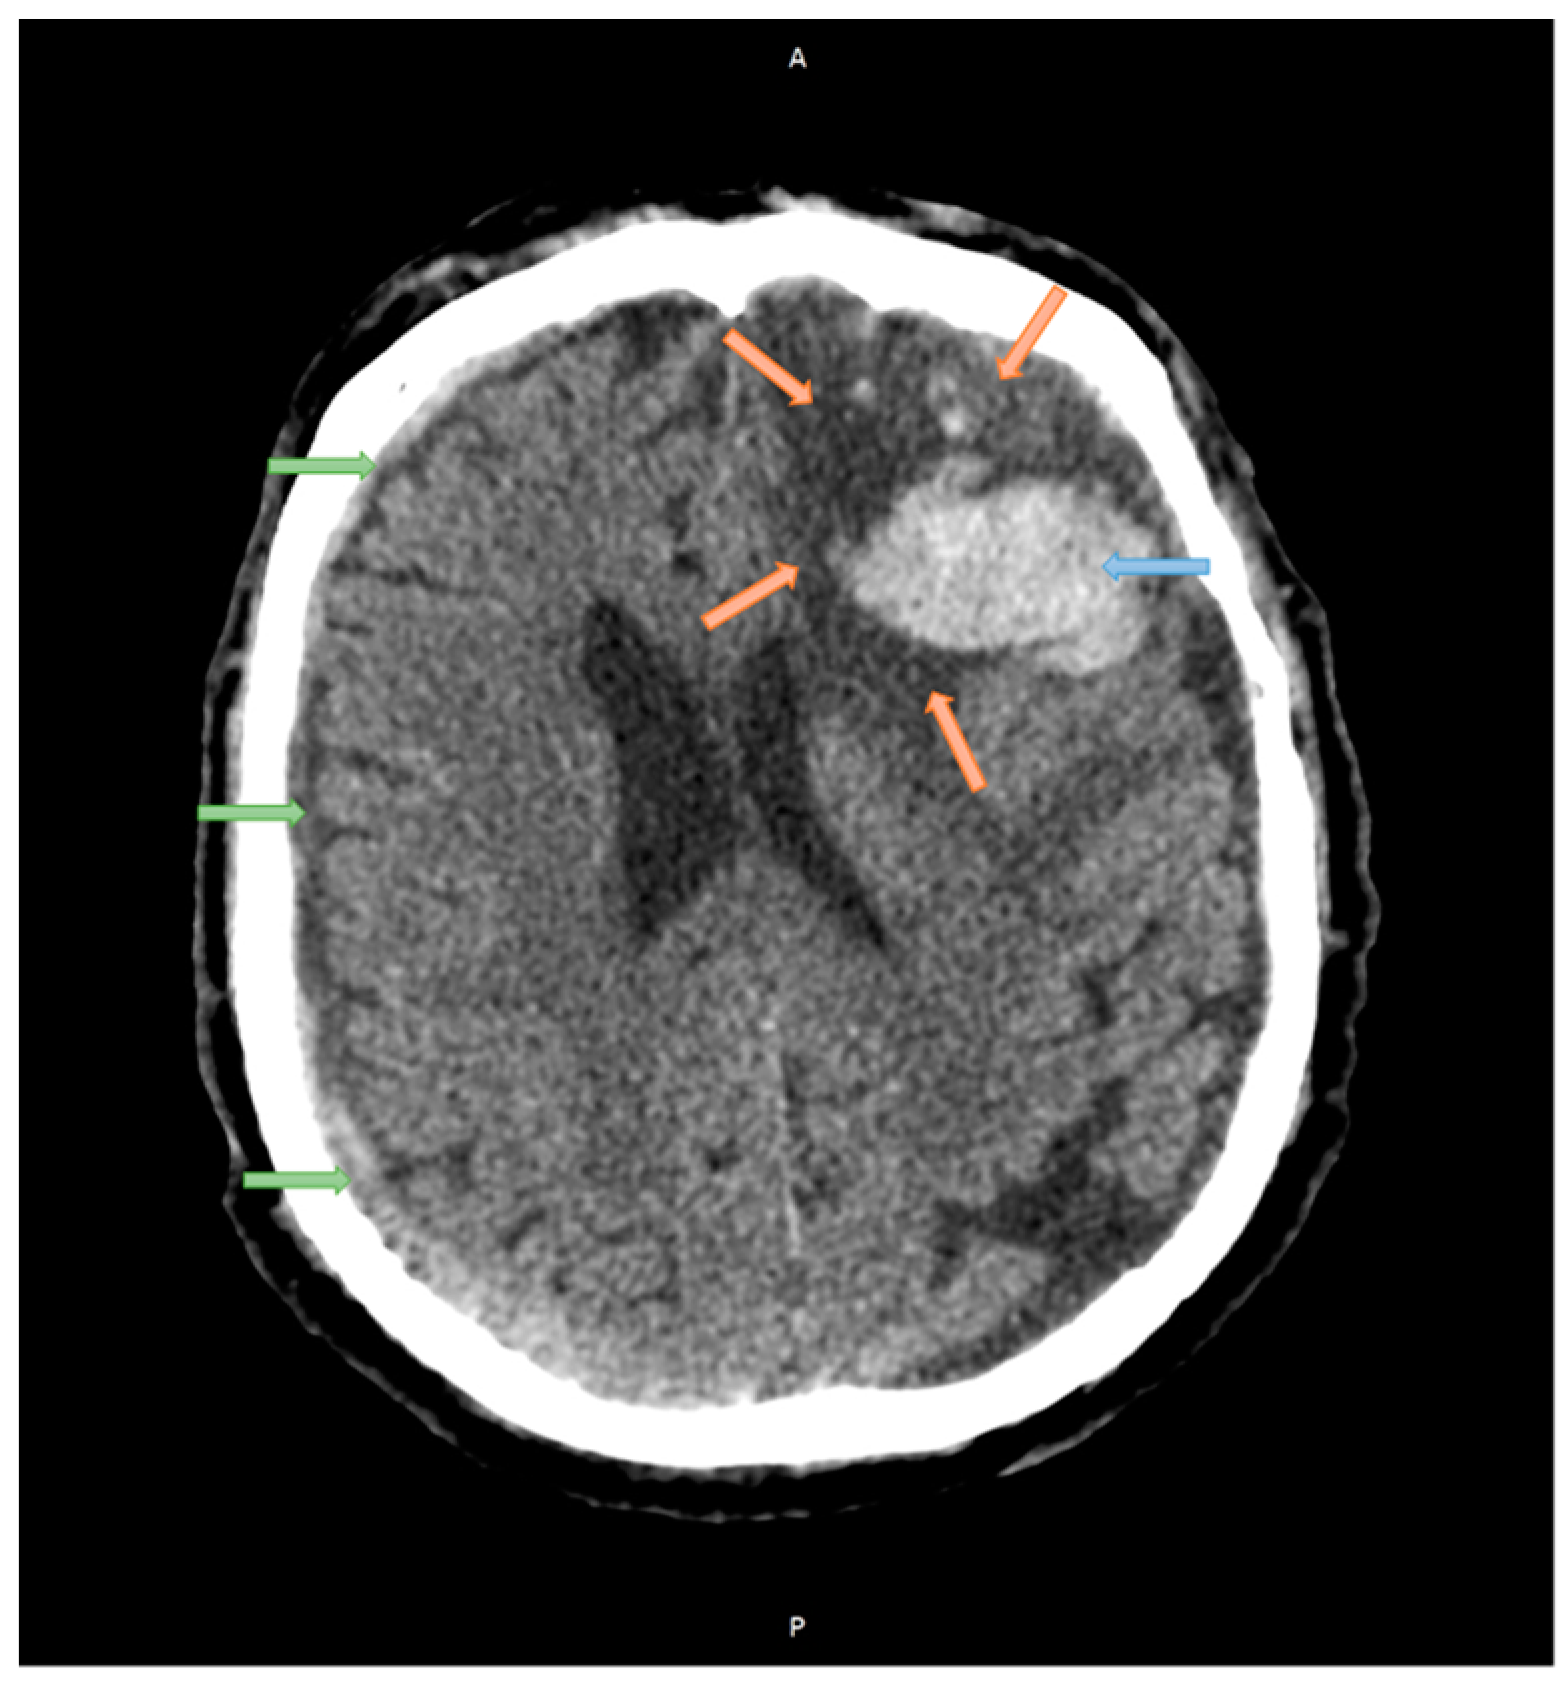

2.1. Case Studies